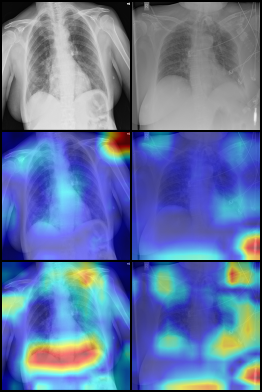

For the covid-qu-Ex dataset, we trained the network with hyperparameters λ=5𝜆5\lambda=5, ρ=0.25%𝜌percent0.25\rho=0.25\%, 2 downsampling steps in the attention network, and 5 downsampling steps in the replacement network. We used a learning rate of 21042superscript1042\cdot 10^{-4} for both the lens and classifier. As there is no validation set without shortcuts for covid-qu-Ex, we evaluated the effectiveness of the lens in identifying shortcuts using GradCAM [22]. Figure 4 shows the GradCAM images for all three classes and both trained networks. From these experiments, we made several observations. First, without the lens, the network predominantly focused on areas in the corners of the images, mostly in areas with text. Second, with the attention lens, the network focused on more relevant sections of the image, including the lungs. Our proposed approach not only explains shortcuts but also corrects them, as shown in Fig. 5, where highly localized shortcuts such as markers and text are removed.

(a) Normal

(b) COVID

(c) Pneumonia

Figure 4: GradCAM images showing network attention when training on the covid-qu-Ex dataset. Row 1 is the input image from the validation set. Row 2 is the classifier attention of a network trained without, and Row 3 with our proposed model.